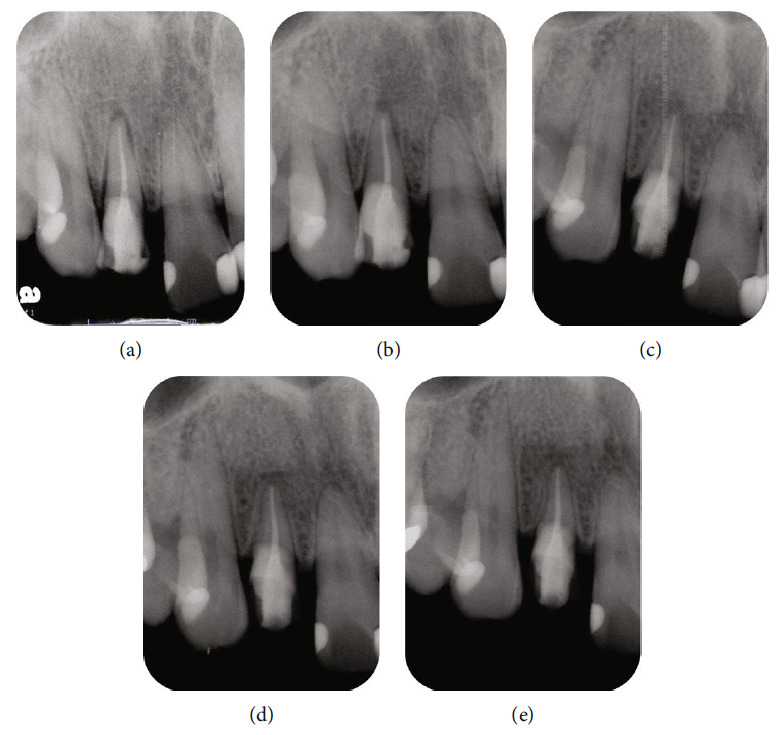

Follow-up appointments were scheduled at various time points (Figures 5(a), 5(b), 5(c), 5(d), and 5(e)). After one week, the sutures and resin cement were removed. Three months after intentional replantation, a provisional restoration was fabricated. RCT was performed with the split dam isolation due to the risk of periodontal exudate contaminating the canal. The tooth was observed for a prolonged period after obturation, with no subsequent symptoms or abnormal findings evident clinically or radiographically. After determining that additional root canal retreatment was not necessary based on a 6-month follow-up, a composite resin crown (Kuraray Noritake Dental Inc.) was constructed using computer-aided design/computer-aided manufacturing as the final step in the restoration process. There were no clinical symptoms during this period, and radiographs showed no detrimental effect of intentional replantation. Furthermore, no clinical symptoms or abnormal findings were observed 18 months after intentional replantation. These results demonstrate the success of ECR treatment with RCT and intentional replantation (Figure 6).

Figure 5.

Radiographic images after intentional replantation. (a) Intraoral radiographic image was taken immediately after intentional replantation with crown rotation. (b) Intraoral radiographic image was taken one month after intentional replantation. The periodontal ligament space appears to be slightly larger than that immediately after intentional replantation (c) Intraoral radiographic image was taken three months after intentional replantation. The periodontal ligament space is similar to that around the adjacent teeth. (d and e) Intraoral radiographic images were taken six months and one year after intentional replantation, respectively. Low-contrast component resin crowns are bonded with adhesive resin.